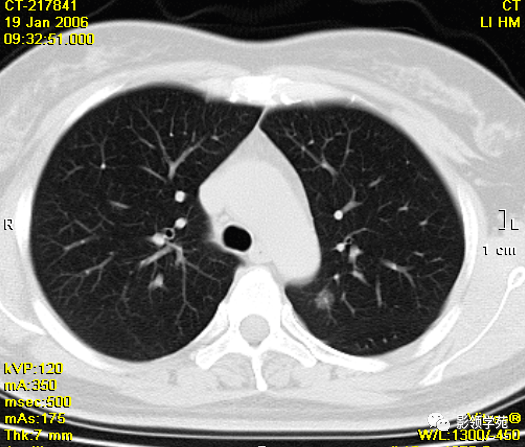

胸部ct

细支气管肺泡癌的影像学